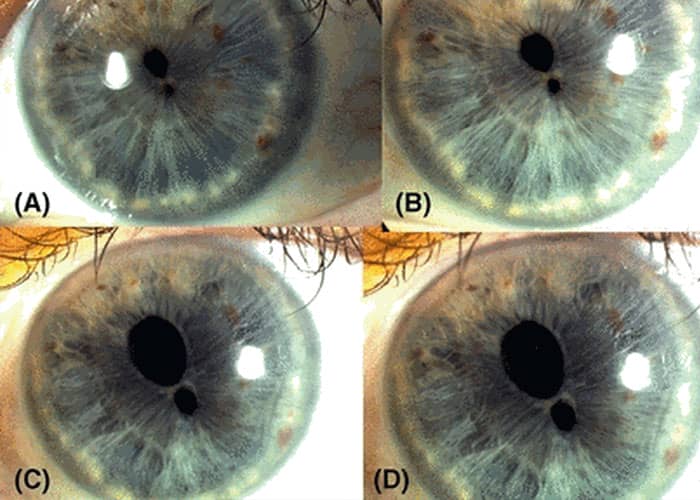

I went to school with twin sisters who were identical in every way – except for their eyes.

Both of them had heterochromia, but their eye colours were strikingly different to each other.

Twin one had a green right eye and blue left eye. Twin two meanwhile had a hazel right eye and a blue-grey left eye.

I knew someone who had one fully brown eye, and one eye that was 3/4 brown and 1/4 blue. Just a pizza-slice-shaped chunk of pure blue amidst the brown.